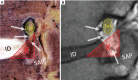

Figures